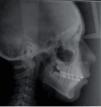

In the treatment progress lateral headfilm a significant change occurred in the profile and at dental level. The latter was corroborated with the following cephalometric measurements: Upper incisor to SellaNasion, upper incisor to palatal plane, lower incisor to mandibular plane, interincisal angle, nasolabial angle and mentolabial angle. These values showed an upper incisor retroclination, lower incisor retroclination and a change in soft tissues (Figure 8).

In the lateral headfilm it may be observed that the hyper-divergent skeletal class I was maintained with a slight dental change compared with the progress analysis. In the panoramic X-ray an acceptable root parallelism is noted as well as the eruption of the third molars (Figures 12 and 13).